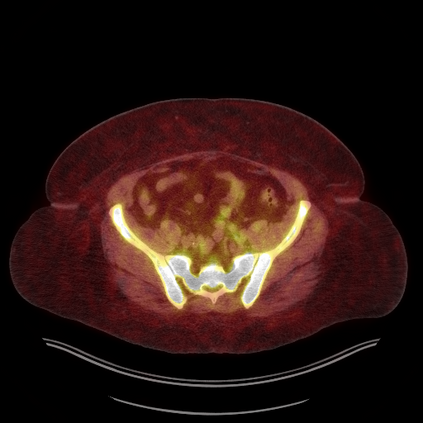

Medical images play a crucial role in assisting diagnosis, remote consultation, and academic research. However, during the transmission and sharing process, they face serious risks of copyright ownership and content tampering. Therefore, protecting medical images is of great importance. As an effective means of image copyright protection, zero-watermarking technology focuses on constructing watermarks without modifying the original carrier by extracting its stable features, which provides an ideal approach for protecting medical images. This paper aims to propose a fragile zero-watermarking model based on dual quaternion matrix decomposition, which utilizes the operational relationship between the standard part and the dual part of dual quaternions to correlate the original carrier image with the watermark image, and generates zero-watermarking information based on the characteristics of dual quaternion matrix decomposition, ultimately achieving copyright protection and content tampering detection for medical images.